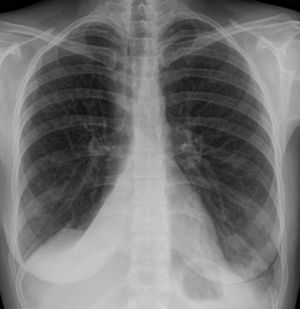

همود الرئة.

التشخيص

• الأشعة السينية للصدر (الانخماص ما بعد العمليات الجراحية يظهر في الجزء الأدنى من الرئتين)

• التصوير المقطعي

• منظار الشعب الهوائية